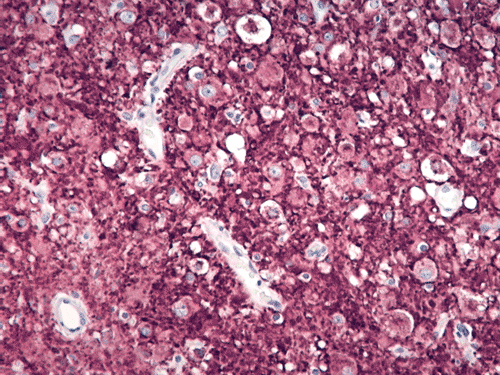

The excised specimen gave the features of cerebellum with greatly expanded cerebellar folia with myelination on the surface of the folia (Panel A, letter S indicates the material used to support the specimen) which can be seen easily on fresh specimen. . The expanded folia are most obvious in fixed specimen (Panel B). On pendicular section of the specimen (Panel C, arrow head points to the pial surface), the normal archicheture of cerebellum is totally effaced. The outer layer is composed of a layer of white matter while the inner half is composed of collections of large, ganglion cells ( in indicates the interface of the two layers which is magnified in Panel D). Multiple calcifications (darks spots in Panel C) are also present.The deeper layers of ganglion cells are composed of large, ganglioinic neurons of similar size and separated by only a small amount of glial tissue (Panel E and F). Multiple calcifications are seen in the more superficial layer of white matter (Panel G). Many calcified blood vessels (Panel H) are also noted in the deeper layers with ganglionic cells. The superficial white matter layer is well myelinated and strongly reactive for neurofilament (Panel I and J, stained by Luxol fast blue- Creysl Violet and immunohistochemistry for neurofilament respectively correspond to the interface indicated by the * in Panel C). The ganglionic cells are stronly reactive for neurofilament protien and synaptophysin (Panel K and L).

Histologically, a layer of myelinated fibers with large diameter myelinated axons is present in the more superficial location of the expanded where the molecular layer is found at the same level in normal cerebellum. The deeper layer where internal granule layer is supposed to be found is replaced by sheets intermediate sized to large dysplastic neurons that resemble Purkinje cells. In high magnification, these areas resemble gangliocytoma. The proportion of the myelinated outer layer and ganglionic inner layer is variable. The normal Purkinje cell layer is not found. Interspersed in between are much smaller neuronal cells with hyperchromatic, small nuclei that resemble hte internal granular layer. This is, therefore, essentially an “inside-out” architecture of the cerebellum with white matter on large ganglionic neuronal layer in the deeper layer. Mitotic figures are exceptional. Ki-67 labeling is 0-2% for the small number of cases that have been studied. The native white matter of the affected folia is atrophic and rarefied. The histologic features are very specific. Immunohistochemistry is not typically required for diagnosis.